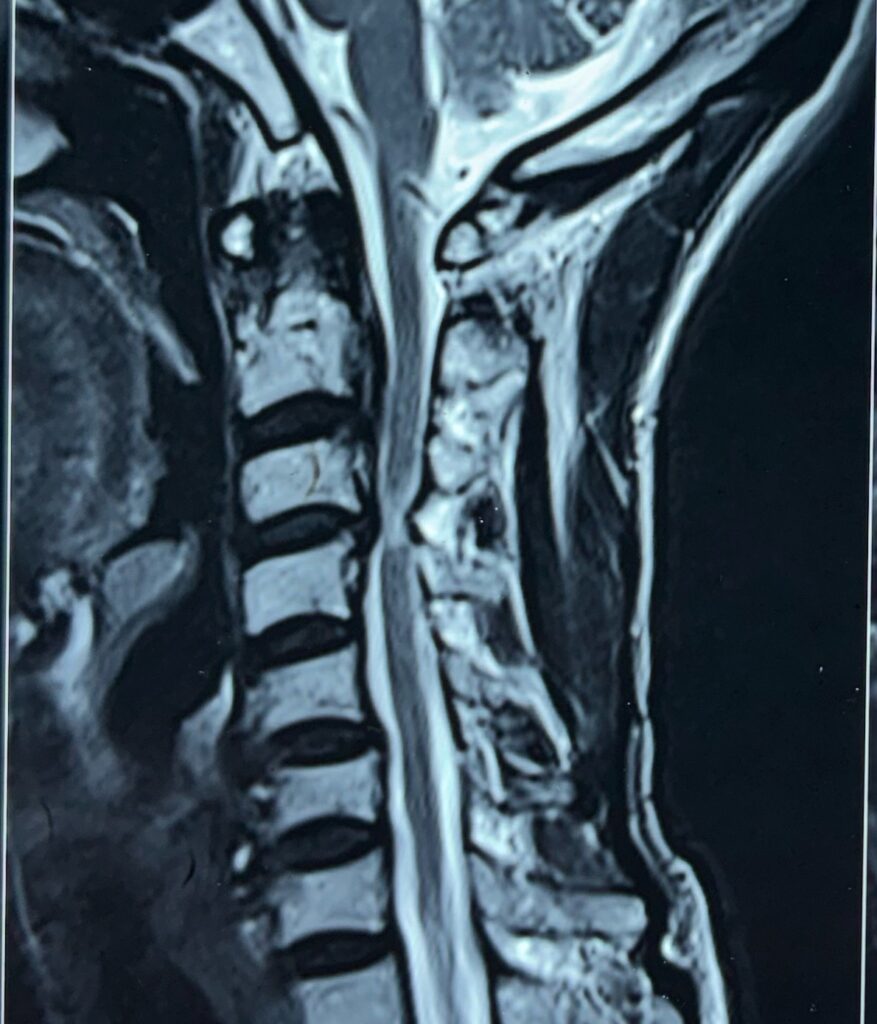

- MRI scan: To check spinal cord, discs, and nerve damage

- CT scan: Provides detailed images of the spine structure

3. Surgical Treatment (When Needed)

Surgery is required in severe cases when:

- There is spinal instability

- The spinal cord or nerves are compressed

- There is loss of movement or sensation

Cases treated by Spine Specialist Dr. Gaurav Sandeep Gupta